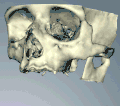

Методы, используемые для планирования имплантатов

Чтобы помочь хирургу позиционировать имплантаты, сделана направляющая (обычно из акрила), чтобы показать желаемое положение и угол наклона имплантатов.

Иногда окончательное положение и восстановление зубов будут смоделированы на гипсовых моделях, чтобы помочь определить количество и положение необходимых имплантатов.

Компьютерная томография может быть загружена в программное обеспечение CAD/CAM для создания симуляции требуемой обработки. Затем устанавливаются виртуальные имплантаты и на данных 3D-принтер создаётся стент.